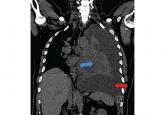

ArticleManaging malignant pleural effusionAuthor:Mateen Uzbeck, MBBSPublish date: February 1, 2019Depending on the circumstances, options are observation, thoracentesis, an indwelling catheter, and chemical pleurodesis.Read More